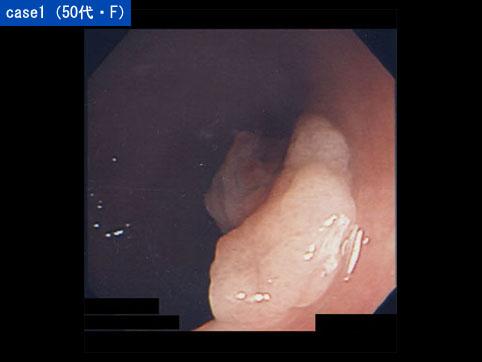

症例提示(所在地,施設名等): 福岡県・ 九州大学病院 (放射線科、宇都宮尚先生からの提供症例)

疾患(病理主体)の分類良性上皮性腫瘍/腺腫

部位(臓器別)大腸/直腸

検査方法内視鏡

腫瘍の肉眼分類0型(表在型)/I型(Is)

病変の最大径(ミリ)10〜14